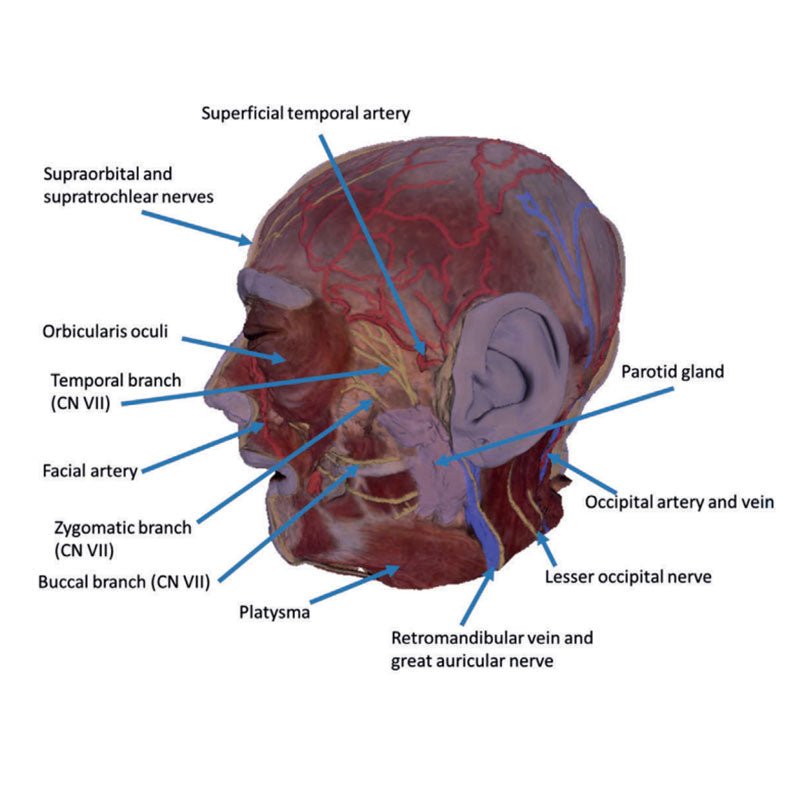

3D Printed Superficial Facial Nerves & Parotid Gland

This 3D model presents the superficial anatomy of the face and head, and compliments the superficial facial anatomy

of our HW 44 model with a more expanded dissection across the scalp and occipital regions.

The superficial

neurovascular and muscular structures in the face largely mirror the structures described in reference to our HW 44

specimen (see description), although the terminal branches of the facial nerve (CNVII) can be largely followed

across a longer course from the parotid gland and the platysma muscle has been retained superficial to the mandible

and extends towards the neck.

In contrast to the HW 44 specimen, this model has a more expansive superficial

dissection inferior to the external ear and across the posterior scalp and occipital region. This allows for an

expanded appreciation of the neurovascular distribution of the supraorbital and supratrochlear nerves and arties

with the superficial temporal artery. Inferior to the ear, the retromandibular vein has been exposed with the

ascending fibres of the great auricular nerve on its superficial surface (and further branches of this nerve on the

surface of the sternocleidomastoid muscle). At the posterior border of the sternocleidomastoid muscle the lesser

occipital nerve is just preserved, near the exiting and ascension of the occipital artery and vein near the

trapezius muscle towards the posterior scalp. Surrounding the external ear are fibres of the auricularis superior

and posterior muscles. Near the margin of the dissection window posteriorly the deep fibres of the occiptalis muscle

can be seen integrated into the epicranius (occipitofrontalis) muscle.